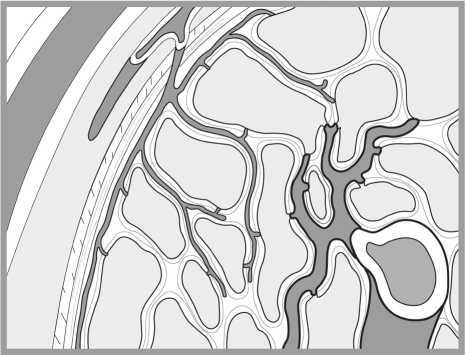

![]() Рис. 5. «Соитие». Рисунок из дневников Леонардо да Винчи (1475–1518 гг.) В одном из рисунков, содержащихся в известных «Дневниках» Леонардо, — «Фигура соития» — изображен срез гениталий мужчины и женщины во время полового акта стоя. Рисунок отражает его понимание, что член входит во влагалище, как ключ в замочную скважину. Он писал: «Женщине нравится, чтобы пенис был как можно крупнее, тогда как мужчина желает от женского чрева обратного». Недавние рентгенологические исследования с трехмерной реконструкцией изображения позволили уточнить анатомические соотношения гениталий в процессе полового акта; эти данные во многом подтвердили представления Леонардо до Винчи. Статья «Магнитно-резонансное изображение мужских и женских гениталий в процессе соития»11 получила в 2000 году Шнобелевскую (антинобелевскую) премию, что свидетельствует как минимум о проявлении интереса к данному исследованию. ![]() Рис. 5 а. МРТ гениталий в процессе полового акта. В период, когда Леонардо занимался изучением строения человеческого тела, в средневековой Европе господствовали медицинские взгляды греческого ученого Галена (131–217). Он считал, что всем человеческим телом управляет «внутреннее тепло» (воздух). Оно же поступает в пенис и вызывает эрекцию. Еще до систематических анатомических исследований, начавшихся с 1503 года, Леонардо присутствовал на публичной казни через повешение и затем вскрытии трупов этих преступников. Он пишет: «Я видел мертвецов с эрегированным членом, что часто происходит у тех, кого казнят повешением. Их пенисы были очень плотны и тверды и наполнены большим количеством крови». Догадка о возникновении эрекции в результате интенсивного притока крови была подтверждена Леонардо да Винчи дальнейшими исследованиями. Амбруаз Паре, которого считают отцом современной хирургии, опубликовал в 1585 году научную работу, содержащую аналогичный вывод. Вероятно, ему не было известно, что на 100 лет раньше это открытие сделал не медик, а великий художник. Однажды бельгийский врач Андреас Везалий (1514–1564), прогуливаясь ночью за городской стеной, набрел на труп повешенного преступника и отрезал у него руку и половой член. Исследовав их, он сделал ошеломляющий вывод: многое из написанного Галеном о теле человека не соответствует действительности. В 1543 году Везалий опубликовал свой труд «О строении человеческого тела» объемом 663 страницы (28 см в ширину, 42 в высоту, в переплете из пурпурного бархата). Как писал Везалий: «В отношении полового члена истина заключается в том, что при акте зачатия этому органу дана такая сила наслаждения, что и молодые, и старые мужчины ощущают потребность размножаться». Анатом и физиолог голландского происхождения Ренье де Грааф завершил к 1668 году самое детальное на тот период исследование строения полового члена. Он использовал свою методику достижения стойкой эрекции членов трупов и значительно превзошел предшественников в понимании ее механизмов. Им доказана не только важная роль интенсивного притока крови к пенису, но и ее стойкого удержания. Гипотеза, что это происходит за счет сжатия мышц, окружающих кавернозные тела, оказалась неверной. Вскоре после опубликования своего труда «Трактат относительно генеративных органов мужчины» он в 1673 году умер, занимаясь лечением больных чумой. Ему было 32 года… Еще один шаг к пониманию строения и функционирования полового члена сделал голландец Фредерик Рюйш (1638–1731). Используя специальный состав жидкости и шприцы, он изготавливал препараты частей тела, словно отлитые из воска. При этом в пенисе были четко различимы артерии и вены. Его модели органов не только были объектом изучения, но также составили коллекции, в которых основными экспонатами служили половые члены. Они были раскуплены европейскими монархами, включая царя Петра I. ![]() Рис. 6а. Кавернозная ткань во время расслабления пениса. ![]() Рис. 6б. Кавернозная ткань во время эрекции пениса. Чтобы закрасить оставшиеся белые пятна в истории познания строения и эрекции полового члена, опишем последние крупнейшие открытия в этой области. В самом начале XXI столетия к урологам пришло понимание, что именно за счет расслабления гладкой мускулатуры, которая входит в состав мельчайших артерий (артериол) и ячеек (синусоидов), кавернозная ткань способна принять и удерживать достаточное количество крови для создания ригидности (твердости) полового члена. При быстром расслаблении этой гладкой мускулатуры артериолы расширяются, сопротивление поступающему потоку крови резко падает, а увеличившаяся в объеме кавернозная ткань прижимает к белочной оболочке и сдавливает вены, по которым кровь могла бы утекать (окклюзия вен). Притекающая кровь оказывается как бы в ловушке, давление в кавернозных телах резко нарастает и становится выше артериального систолического. Однако трофика (питание) тканей члена не нарушается, так как минимальный уровень притока и оттока крови сохраняется. Эти предварительные сведения и выводы были подтверждены последующим изучением анатомии пениса с использованием сканирующей электронной микроскопии. Оставалось неясным, что представляет собой вещество, вызывающее расслабление гладкой мускулатуры кавернозной ткани и расширение ее сосудов и синусоидов. Эту загадку независимо друг от друга разгадали трое ученых: Роберт Фарчготт, Луис Игнарро и Ферид Мурад. Им удалось доказать, что молекула оксида азота (NO), вырабатываемая эндотелием сосудов, и является тем самым веществом, которое вызывает расширение всех периферических (мельчайших) артерий. Основные научные исследования относятся к 1992 году. Позднее авторы стали лауреатами Нобелевской премии (1998) за работу «Монооксид азота как сигнальная молекула в сердечно-сосудистой системе». Все сосудистые реакции, осуществляющие эрекцию, контролируются нервной системой. Ее активное участие в этом процессе впервые установил в 1863 году немецкий ученый Конрад Экхард. Он обнаружил напряжение члена собаки при воздействии на тазовые нервы электрическим током. |